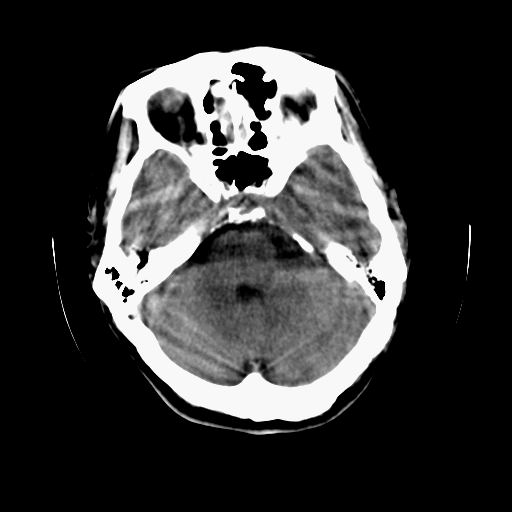

标题: CT13217:头部外伤三月余,头痛三天 [打印本页]

标题: CT13217:头部外伤三月余,头痛三天

血肿是急性、亚急性、还是慢性,要结合外伤时间考虑的,本例头部外伤三个月,应该是明显的慢性硬膜下血肿,但血肿的等密度显然不符合病理改变,估计是合并再次出血,中线结构移位明显,有脑疝形成。应穿刺减压。

血肿是急性、亚急性、还是慢性,要结合外伤时间考虑的,本例头部外伤三个月,应该是明显的慢性硬膜下血肿,但血肿的等密度显然不符合病理改变,估计是合并再次出血,中线结构移位明显,有脑疝形成。应穿刺减压。 大于2个月为慢性出血,2周到二个月为亚急性出血